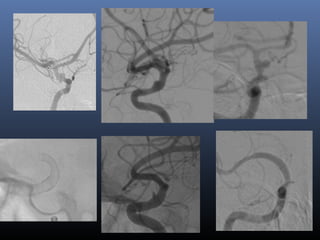

Classical blister aneurysm

34-year M, SAH

Stent …

Further evolution –

flow diverters (stents)